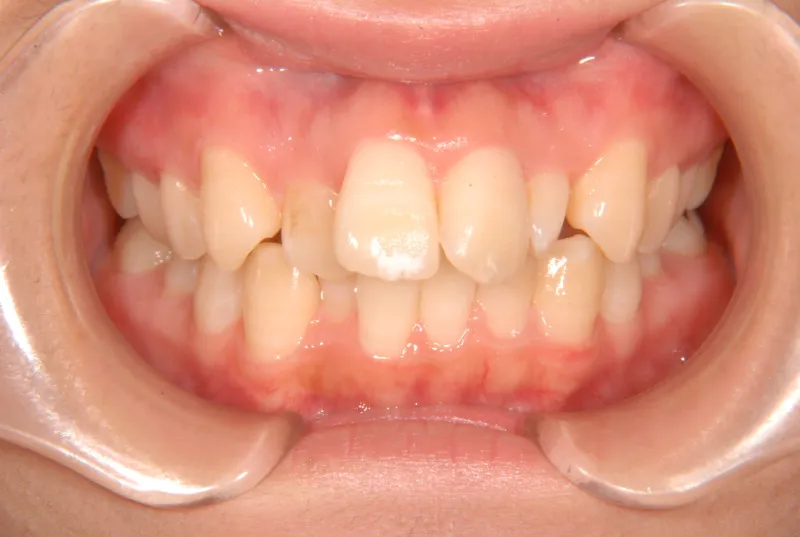

初診時年齢 19~29歳 (女性) 主訴 ガタガタ・90度ねじれている

診断名 叢生・上顎前突 装置名

奥歯が内側と前方にかたむき上下の歯がガタガタに生えています。

90度ねじれた歯もあります。前歯も出っ歯になっています。

歯は抜かず、歯科矯正用アンカースクリューを用いて治療しました。